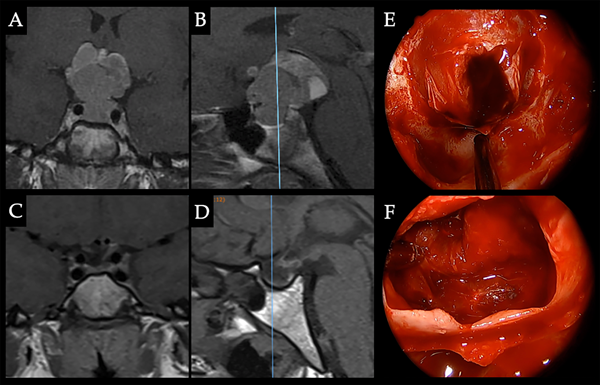

Caso 5. Alteraciones visuales. Paciente femenina de 47 años que consultó por alteración del campo visual y cefalea. PRL: 47 ng/ml. Se decidió resección quirúrgica. Se logró resección completa con normoprolactinemia postoperatoria y mejoría del CVC. A. RM preoperatoria donde se observa adenoma selar-supraselar con compromiso de la vía óptica. B-C. CVC con hemianopsia bitemporal con extensión nasal. D. RM pop con resección completa. E-F. CVC pop con mejoría. G. Imagen intraoperatoria donde se reconocen reparos anatómicos selares y el adenoma luego de la apertura dural. H. Cavidad sin lesión residual, descenso de la cisterna supraselar y remanente glandular a derecha.